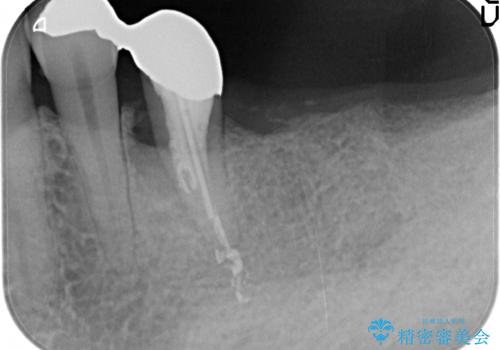

予後の不安な小臼歯と、すでに大臼歯は2本喪失した状態で咀嚼機能に大きく問題がある状態です。

グラつきのある小臼歯は、抜歯を行い2本のインプラントを埋入することでしっかりと咬合機能を回復できる治療を計画します。